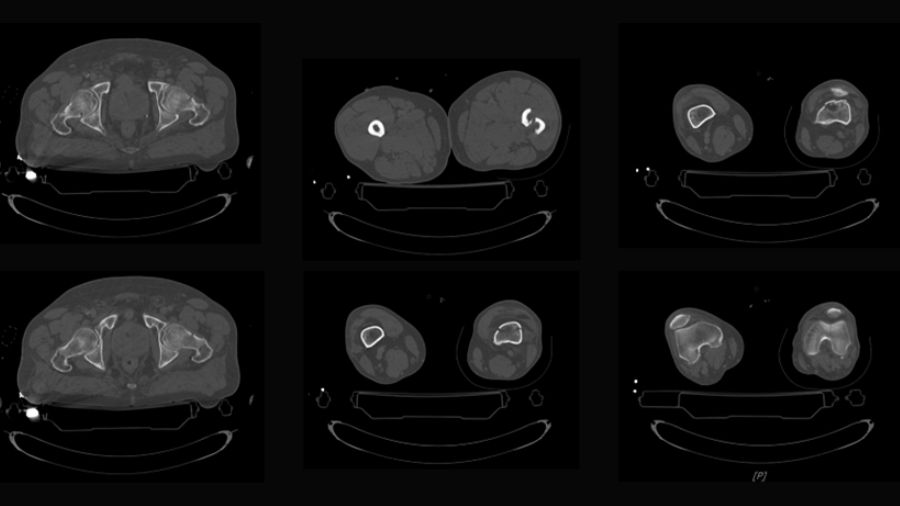

The trifocal femoral fracture (Figure 1) was classified as an obliquely oriented transcervical femoral neck fracture (AO/OTA 31-B2), a displaced shaft fracture (AO/OTA 32-A2), and a supracondylar fracture with intra-articular extension (AO/OTA 33-C2).